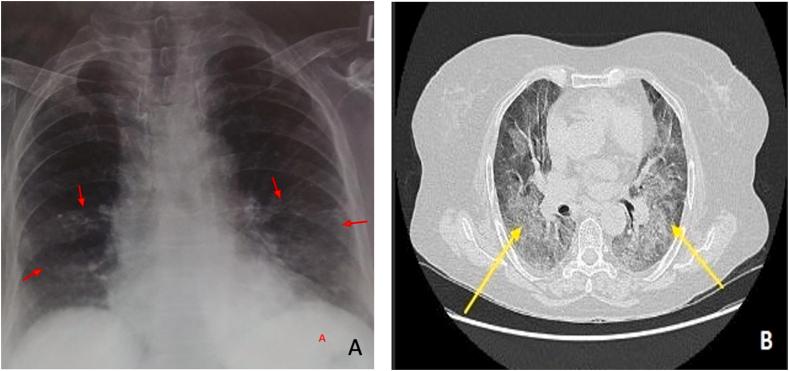

It has been suggested that pulmonary arterial hypertension (PAH) could be a potential sequela of coronavirus disease 2019 (COVID-19) in particular in those with hypertension; however, development of PAH after the course of COVID-19 in normotensive individuals are rarely reported. Here, we report a patient who developed PAH two months post-COVID-19. The patient was a 55-year-old female and normotensive, tested positive for severe acute respiratory syndrome coronavirus 2 (SARS-CoV-2), developed mild respiratory distress syndrome and necessitated continuous positive airway pressure during the treatment in the hospital. After two months discharged from the hospital with RT-PCR negative for SARS-CoV-2, the patient presented with exertional dyspnea, dry cough, fatigue and episodes of syncope during exertion. Based on clinical presentation, electrocardiography, computed tomography, and transthoracic echocardiography assessment, PAH diagnosis was made. To our knowledge, this is a rare PAH case and this highlights the possible of PAH as sequala that might present in post COVID-19 patients.